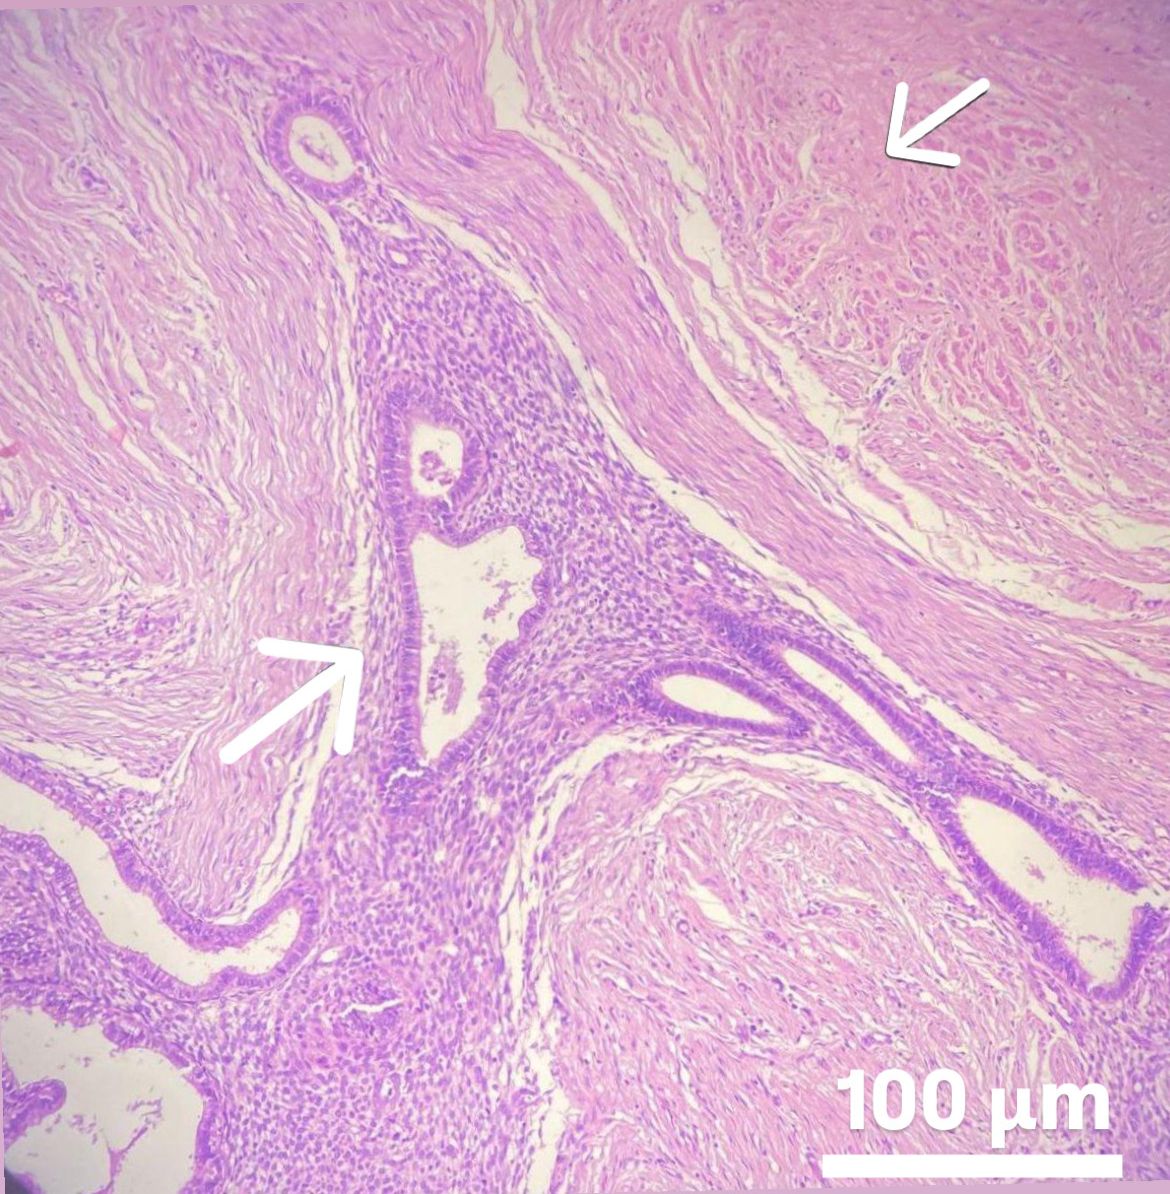

Myoma patients presented to the gynecology clinic due to complaints of prolonged menstrual bleeding and dysmenorrhea. During the transvaginal ultrasound (TVUS) examination, an intramural myoma was detected in 105 patients, submucous myoma in 35 patients, and intramural and submucous myoma detected in 60 patients (Figs. 1,2). Ovarian endometriosis was present in 105 of these patients. These patients were operated on by gynecologists. Pathology results were compatible with leiomyoma uteri (Fig. 3). The hospital stay was for 2 days. In the postoperative period, surgical site infection developed in 6 patients and hematoma at the incision line in 3 patients. Hematoma drainage was performed in only 1 patient. Surgical site infection resolved with antibiotic treatment. During the follow-up period, abdominal wall endometrioma developed only in the patient who underwent intervention due to myomectomy + ectopic pregnancy at the same time (0.5%). Characteristics of the 3 groups are shown in Tables 3,4.

Fig. 3. Microscopic appearance of intramural myoma. The white line marked with a white arrow in the image delineates the border between the leiomyoma and the adjacent myometrium. Endometrioma tissue is visible on the left side. The myometrium in the lower right corner appears distorted due to pressure, while an intramural myoma is observed in the upper left corner. Scale bar: 100 μm (H&E, hematoxylin and eosin,